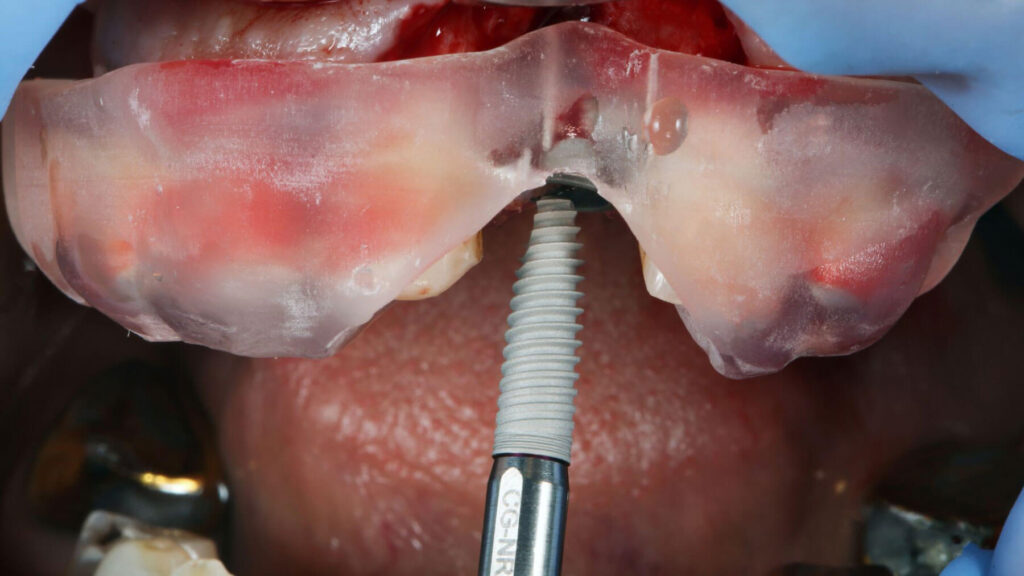

During the implant placement procedure, the titanium posts are surgically inserted into the jawbone. This step is typically performed under local anesthesia.

Healing and Osseointegration

Next, you allow time for healing and osseointegration (fusion with bone), which supports long-term stability.

Implant-Supported Dentures: Enhanced Stability

Implant-supported dentures attach to implants, which can improve stability and reduce slipping.